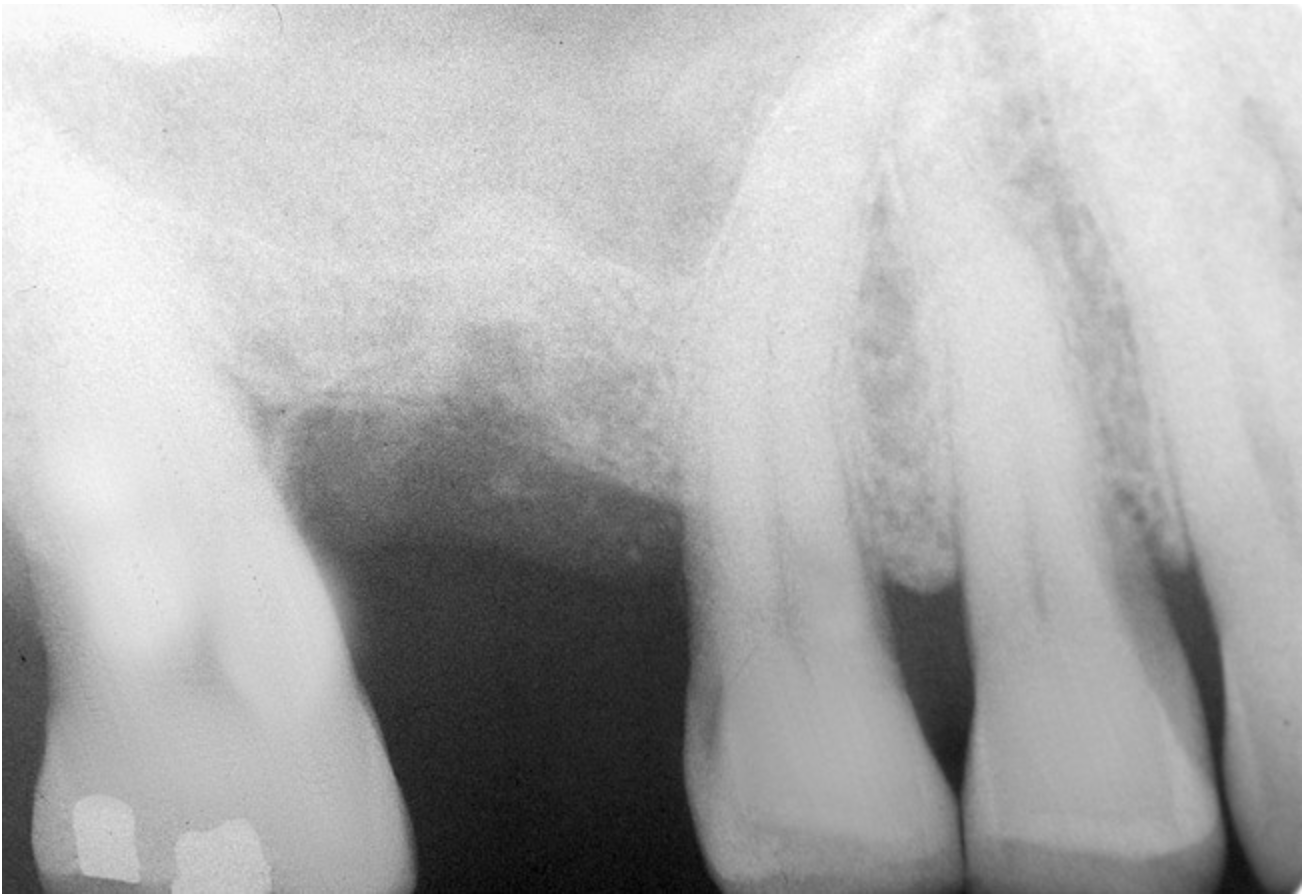

Accidental Penetration of Sinus Membrane with First Twist Drill

When using a 2-mm twist drill, the sinus could inadvertently be entered. This incursion can be verified by occluding the patient's nostrils and having the patient blow (Valsalva maneuver). If the membrane has been perforated, air bubbles will appear in the osteotomy. Some clinicans indicate that if a perforation has occurred, the sinus floor elevation procedure should be aborted and the site should be allowed to heal for 4 weeks and then redone.4 However, the situation may be salvageable (Figure 12, Figure 13, Figure 14, Figure 15). The amount of bone that is subantral can be re-evaluated, and then the second drill (eg, 2.8-mm wide) used, making sure not to enter the sinus. Similarly, the third drill (3.5-mm wide) can be used to proceed 1 mm short of the sinus floor. The initial sequence should be followed with respect to adding bone; whether or not a dome has formed should be verified radiographically. If the graft material is contained, then the procedure can be brought to conclusion as if a perforation had not occurred. On the other hand, if the material was not contained, it may appear on the radiograph as a "trail of smoke." In this case the procedure needs to be aborted or a lateral wall sinus lift needs to be performed to complete the task and repair the perforated membrane. In general, the ostium is 2.4-mm wide;33 it ranges from 2.14 mm to 6.77 mm.34 Therefore, particles that have escaped through the membrane will probably be swept through the ostium by the ciliated columnar epithelium without any untoward occurrence. Other authors have also noted that a perforation of the membrane does not necessarily result in failure of an implant that penetrates into the sinus.35

Figure 12  Initial radiograph at site No. 3.

Figure 12

Figure 13  Despite initial perforation into the sinus with the 2.1-mm twist drill, the drilling sequence was continued after the drill depth was adjusted to be 1 mm short of the subantral floor. The radiograph demonstrates that after the subantral floor was up-fractured and bone was added via the osteotomy, the initial puff of bone was contained. Therefore, the procedure could continue.

Figure 13